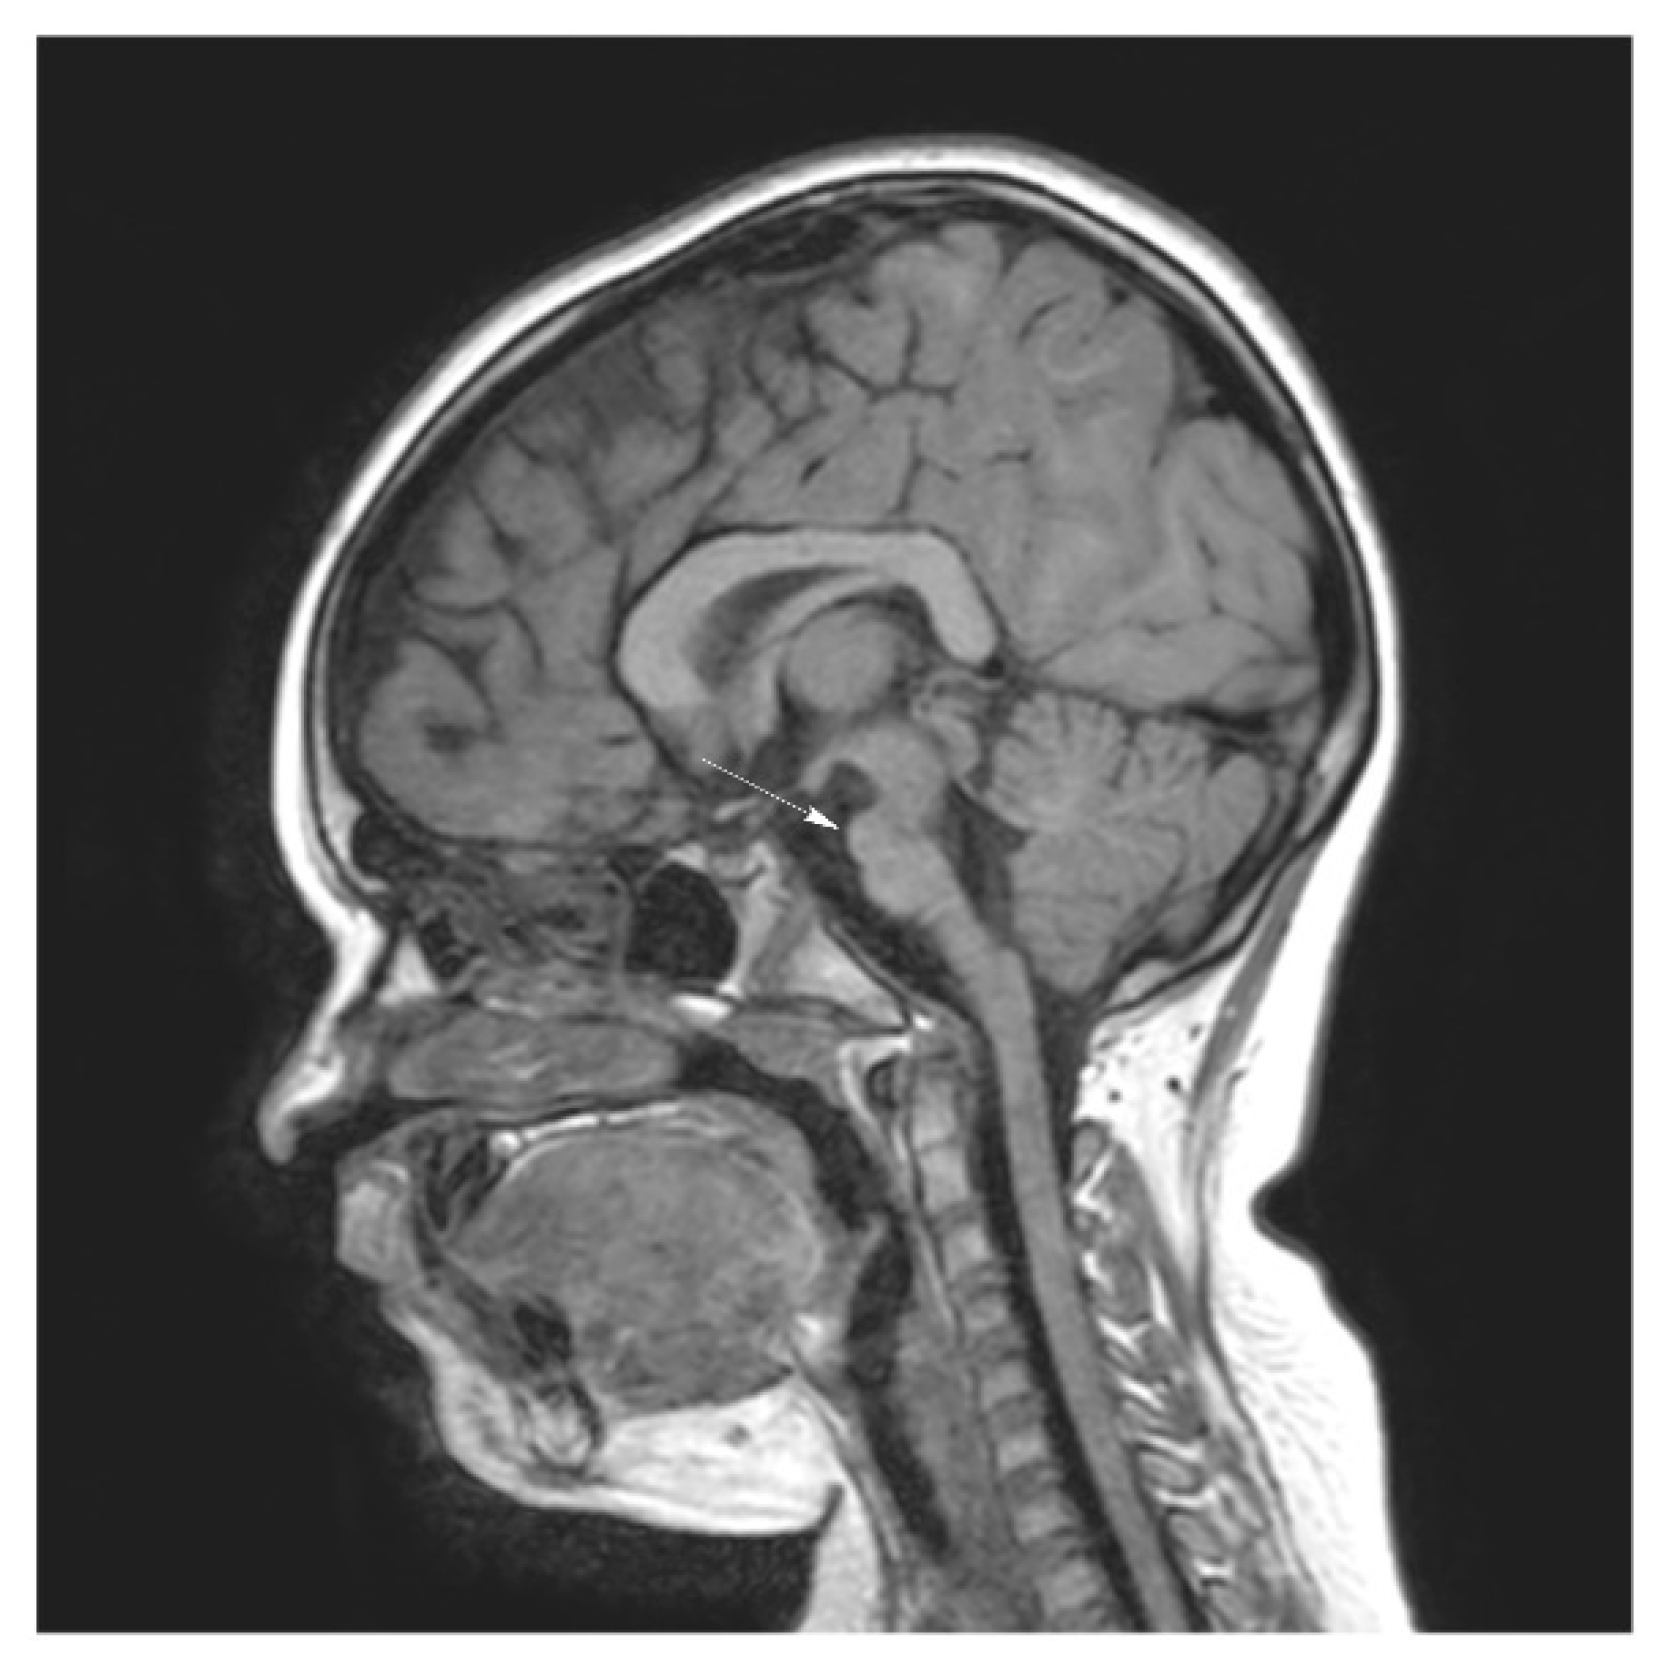

Brain magnetic resonance imaging (MRI) demonstrated hypoplasia of the brainstem (Figure 2), a left thalamus volume larger than the right (Figure 3), an enlarged fourth ventricle, an anterior and posterior midline bulbar and pontine cleft (split-pons sign) (Figure 4), a butterfly configuration of the medulla (Figure 5), an occipital and parietal plagiocephaly on the right side, and a slight benign enlargement of the subarachnoid spaces in the frontotemporal area. There were no signal changes within the medulla or pons in any of the brain MRI sequences.

Figure 2. MRI brain imaging showing hypoplasia of the brainstem.